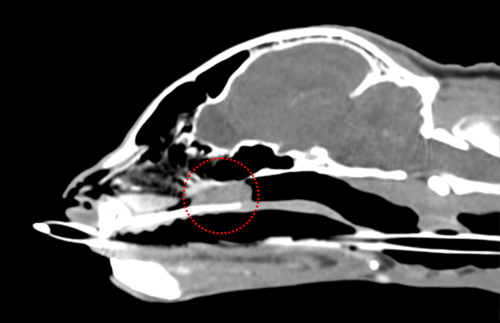

CT, 초음파, X-ray

고양이 영상의학센터

(Feline Imaging Center)

최첨단 영상장비를 통해 더욱 정확한 진단이 가능합니다.